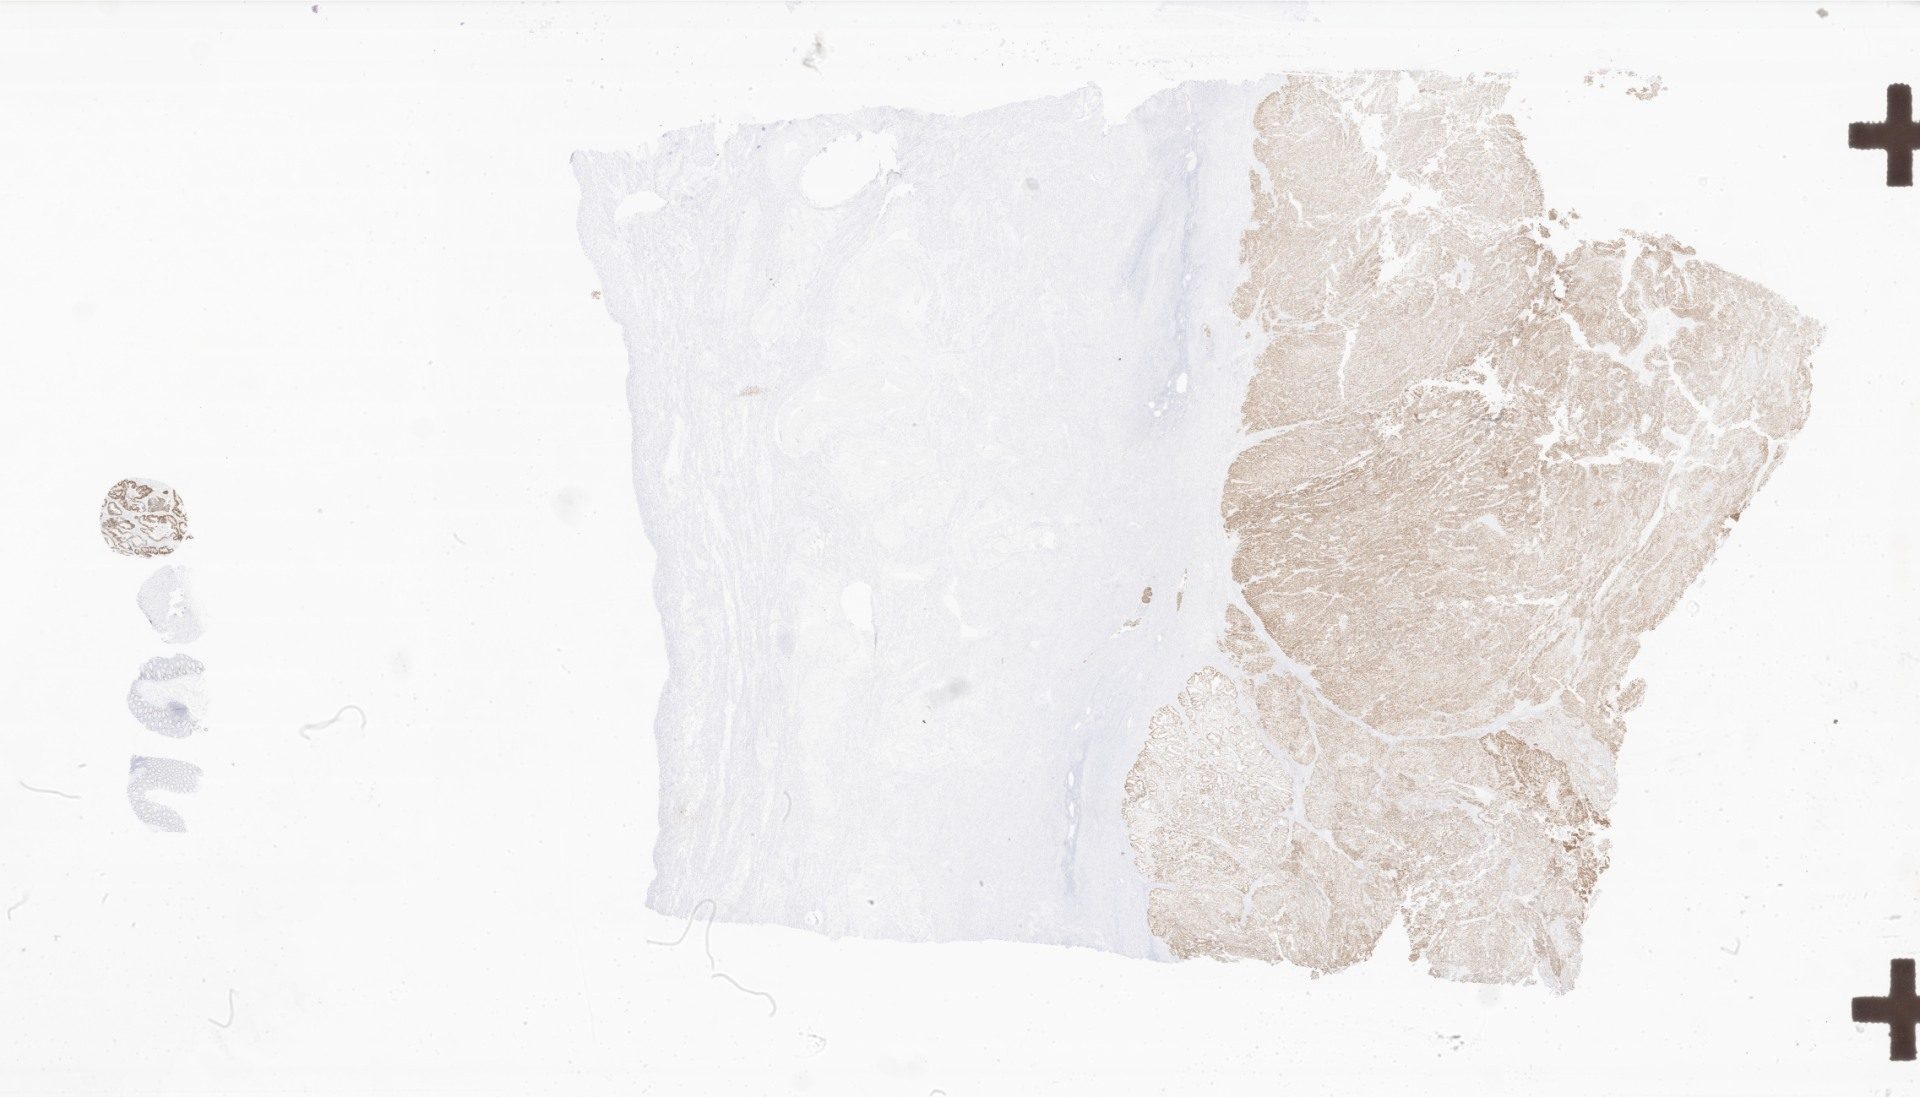

7c029a0f-8703-2fad-664b-95c29dbaa5c5_093723.svs

126201

x

87974

@

40X